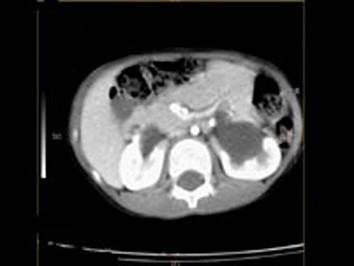

女,6个月,CT扫描如图所示,下列说法错误的是 ( )A、异位肾B、马蹄肾C、双侧肾门朝向前内方D、双肾下极融合E、双侧肾盂积水

问题 女,6个月,CT扫描如图所示,下列说法错误的是 ( )

选项 A、异位肾 B、马蹄肾 C、双侧肾门朝向前内方 D、双肾下极融合 E、双侧肾盂积水

答案 A